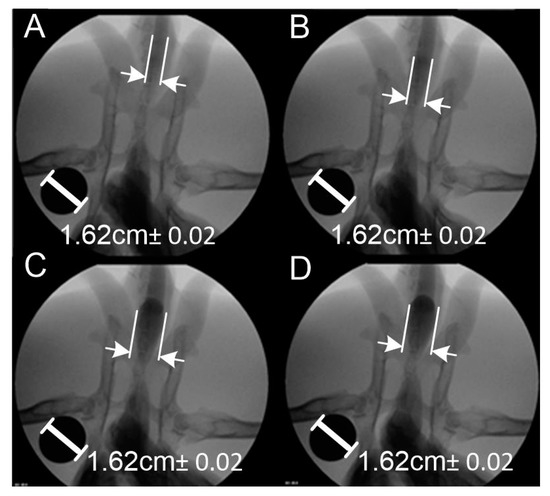

2. Materials and Methods

3. Results